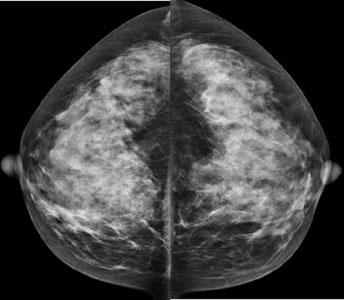

How 3D Mammography and Breast MRI Detect Early Breast Cancer

Breast cancer is one of the most common cancers affecting women worldwide, and early detection is one of the most effective ways to improve survival rates. Throughout the years, medical imaging technology has advanced, making diagnosis more accurate and less invasive. Among these advances, 3D mammography and breast MRI developed as powerful tools for early…